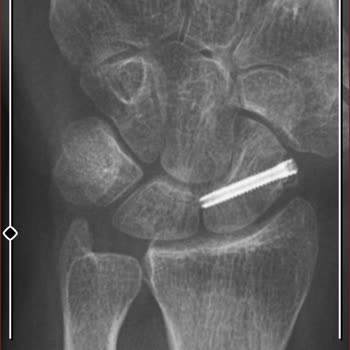

Büyükçekmece Kolan Hastanesi ve baş hekim yardımcısı op. Dr. F*** M*** Ü*** sizinle mahkemede görüşeceğiz. Kırık ayağın iyileşti diyerek çalışabilir raporu verdin! 1. Platin yanlış takılmış ayağım 8 cm önde 2. Platinin vidalarından biri eklemime saplanmış. 3. Yaran kapanıyor dediğin yer et parçası değil enfeksiyon bunu bilmemiş olman ne garip? 4. Sizin aylarca benden almadığınız kanımda enfeksiyon çıktı. 5. Enfeksiyon kırık kemiğime bulaştığı söyleniyor ve kaynadı dediğin kırık kaynamamış bana açık yaranı sarıp işe göndereceğiz demiştin oysa ayağımı tutan kaynayan kemik değil platinin kendisi. Ayağını bas korkma diyordun ya iyi ki ayağıma çok yüklenmedim. Çünkü platinin kırılma ihtimali var. Yani kırılsaydı belkide ömür boyu sakat kalacaktım ya da merdivenlerden yuvarlanacaktım ya da yolda yürürken arabanın altında kalacaktım. 6. Benim röntgenimi çekmeden çalışır raporu vermen yürümeye korkuyorsun demenden atarlı giderli konuşmadan belliydi.  enfeksiyon olduğunu çok iyi biliyordun bu ayağı düzeltemeyeceğinide biliyordun. 7. Benim ayağımın sakat kalma ihtimali varmış. Ameliyat olacağım niye biliyor musun prof Dr. Taktığın daha doğrusu takmayı bile beceremediğin platinler çıkarılacak. Kemiğime enfeksiyon bulaşmış senin sözde aylarca muayene edipte göremediğin enfeksiyon için mücadele verilecek. Enjeksiyon yenilirse ikinci ameliyat olacağım kemik nakli kas nakli bunların 1 yılı bulacağı söyleniyor ve bir garantisi yok prof Dr. Hani diyorum ya fizik tedaviye ihtiyaç yok ayağın iyi şimdi çok iyi anlıyorum niye fizik tedaviye göndermediğini sen gerçekten efsanesin. Yaraya su dökebilirsin demenden belliydi en başından anlamalıydık. Gerçi neyi anlayacaksın telefondan asistanın bana çalışır raporu vereceğiz dediğinde bu işin buraya geleceği belliydi. Sizin hiçbir zaman göndermediğiniz temografide çıktı bunlar. Senin çektiğin normal röntgen de bunlar çıkmıyor yeni Dr. Bu röntgenle bir şey belli olmaz birçok cihaza gönderildim. Baltalimanı op. Doktoru Yani kısaca bu işin uzmanı. Biz sana demiştik ameliyattan sonra bizim yerimiz uzak başka hastanede ilk ameliyattan sonra tedavi olalım. Sen ne dedin Ahmet'in ölüsü de dirisi de benim, ölüyü de diriye de gördük sayende. Kibrin hasmı Allah'tır. İlk ameliyattan sonra benim işim buraya kadar bu kırık beni aşar daha iyi hastaneye ve Dr. Gösterin deseydim bunlar başıma gelmeyecekti.

19.06.2023 tarihinde iş kazası geçirdim, ayağım kırıldı. Büyükçekmece Kolan hastanesinde İlk ameliyatım yapıldı. İlk ameliyattan sonra dikişler alındı. Daha sonra Dr. Bana duş alırken ayağına su dökebilirsin dedi. Bu olay yaramın intihaplanmasına sebep oldu. İkinci ameliyat yapılmasına karar verildi. Ancak doku nakli ameliyat hüsranla bitti. Ameliyatın başarısız olma sebebi platindeki vidanın olmasıydı. Sonra vidayı aldılar. Madem vidayı alacaktınız niye ameliyat yaptınız? Bu ameliyattan sonra ki dönemde verilen raporum hastane tarafından onaylanmadığını SSK tarafından öğrendim. Hastaneyi aradım Dr. Asistanına durumu anlattım. Kendisi bana 27.11.2023 tarihinde geleceksin biz sana çalışır raporu vereceğiz dedi. Şimdi soruyorum hastaneye girmeden röntgen çekilmeden telefondan çalışır raporu vereceğiz denilebilir mi? İlk ameliyat olduğumda hastane uzak olduğu için biz evimize yakın hastane istiyoruz dediğimizde Dr. Bize senin ölünde dirinde benim demişti. Son röntgende vidalar dolmadığını kırık yerlerin tam dolması için zamanın olduğunu yavaş yavaş yürümemi ancak ramboluk yapmamı söyleyen Dr. Ne olduysa bu asistan ile paramı alamıyorum onay niye verilmiyor dedikten sonra hastaneye gittiğimde bana yara açık ayak şiş fizik tedavi olunmamış ayağa çalışır verdi. Üslubu davranış biçimi bir ay önce ki Dr. İle yakından uzaktan olmadı beni hastaneye götüren şirketin sağlık görevlisi tarafından bizzat görüldüğü kendisinin de buna bir anlam veremediğini bilmemizi istiyorum. Bu olaydan sonra şirketin sağlık görevlileri bana bu ayakla iş başı yapmamın mümkün olmadığını ayağımda ödem olduğu yaranın açık olduğunu fizik tedavi olunması gerektiğini belirtildi. Ben bu Dr. Dan şikayetçiyim. Büyükçekmece Kolan hastanesinde ki, Op. Dr. F*** M*** Ü*** hakkında soruşturma açılmasını arz ederim. Saygılarımla. Dip not. Sağlık Bakanlığı da dahil olmak üzere şikayet etmemiz gereken ne kadar yer varsa şikayet yapılacaktır.